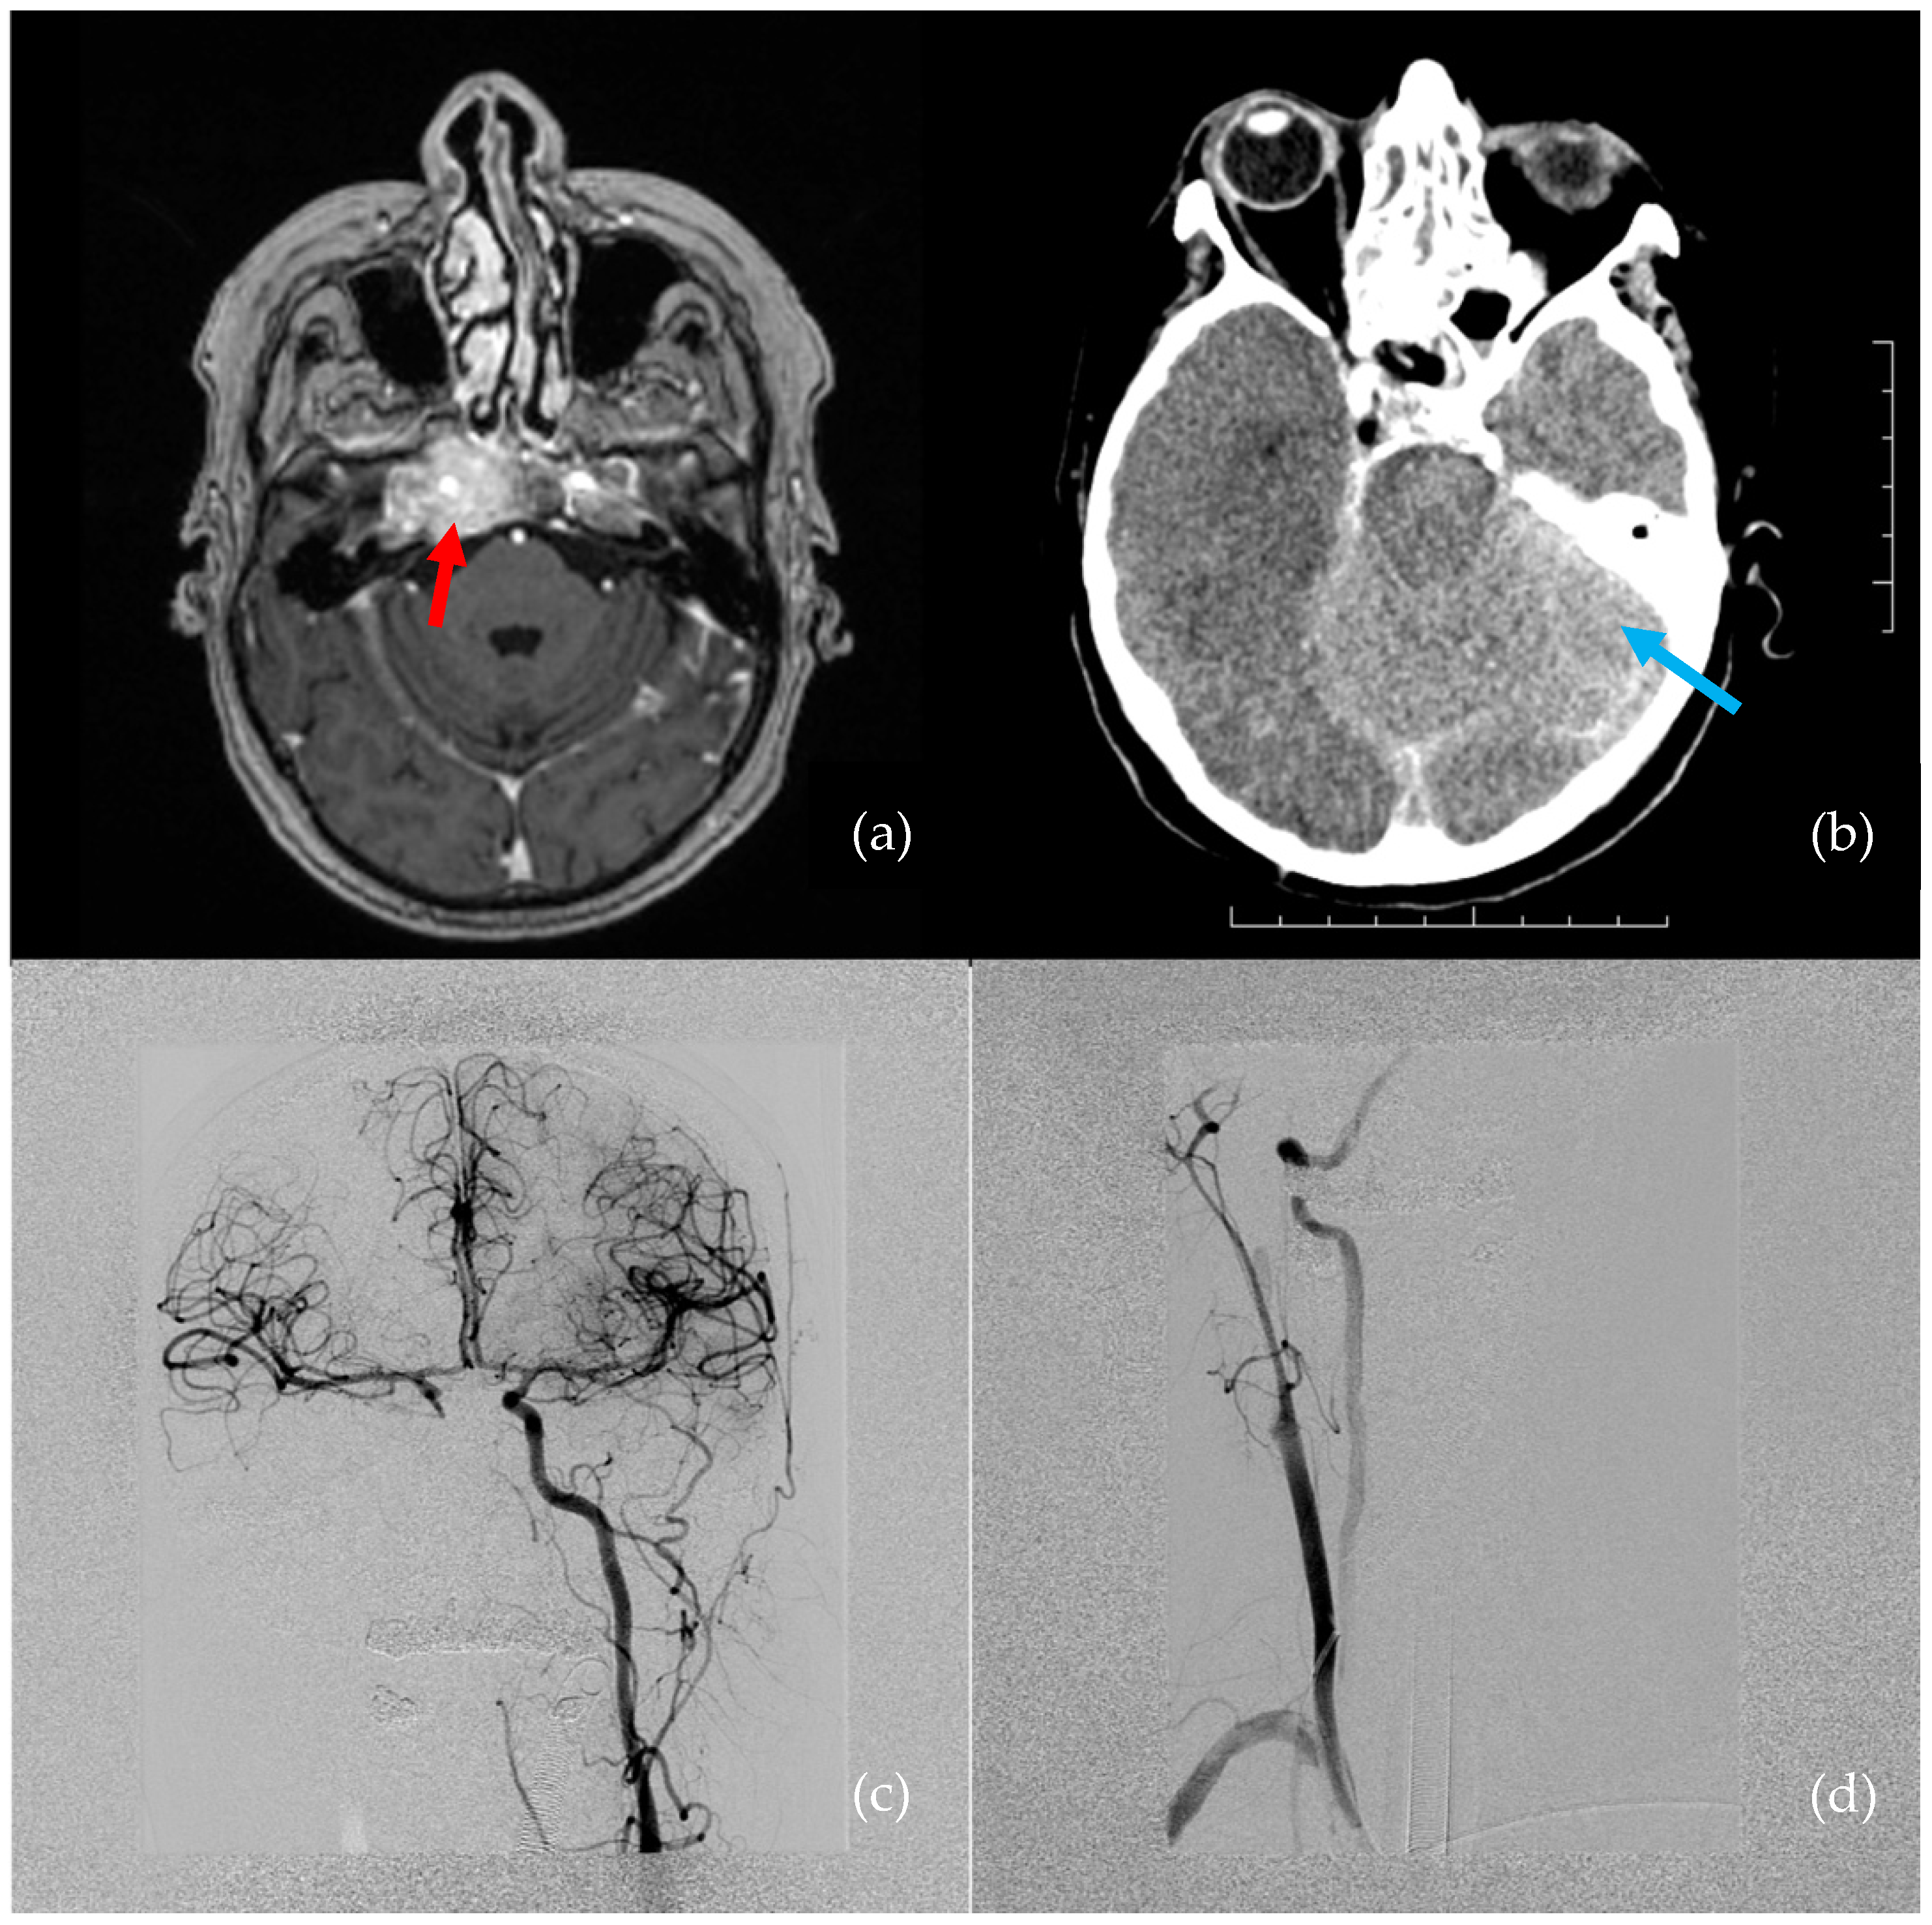

According to the literature, an ICA injury during skull base surgery is a rare, and probably underreported, complication. Although treatment algorithms were proposed by Gardner et al., Kassir et al., and Hamour et al., currently, there is no universal guideline for the management of this complication [7,10,11]. However, it is important to be prepared for it and to agree on an algorithm for managing ICA injuries that is feasible in the specific settings of a particular institution. The algorithm followed in our department is described in Figure 2. For the best results in minimizing morbidity and mortality, a fundamental feature of the algorithm is close cooperation within a broad interdisciplinary team, which comprises otorhinolaryngologists, neurosurgeons, anesthesiologists, interventional radiologists, neurologists, and rehabilitation therapists [6].

Figure 2. Algorithm for managing an internal carotid artery (ICA) injury, developed at the University Hospital Ostrava. ENT: ear, nose, throat; Merocel: polyvinyl acetate packing strips; DSA: digital subtraction angiography.